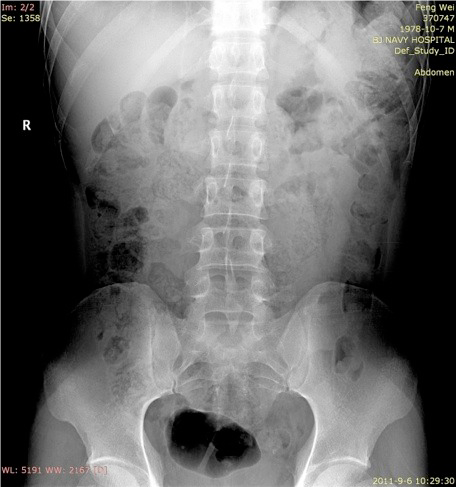

断层容积图片:

影像描述: X线平片:立位X线腹部平片可疑盆腔内(左侧)点状高密度影,但由于肠道气体影响,双肾影无法显示(患者不愿意接受清洁灌肠)。 断层容积图像:去除了肠道气体的影响,清晰显示盆腔内(左侧)点状高密度影,同时显示左肾中部多发点状高密度影。 断层容积诊断: 左侧输尿管盆内段结石,左肾多发结石。 病例点评: 清洁灌肠,是怀疑泌尿系结石时X线腹部平片检查前的常规准备,许多患者不愿意接受这种暴露,接触敏感部位的检查,清洁灌肠也会给患者带来很大的痛苦。断层容积成像完全不需要清洁灌肠准备。肾结石,输尿管下端结石同时显示,说明断层容积成像能大范围清晰显示病变。